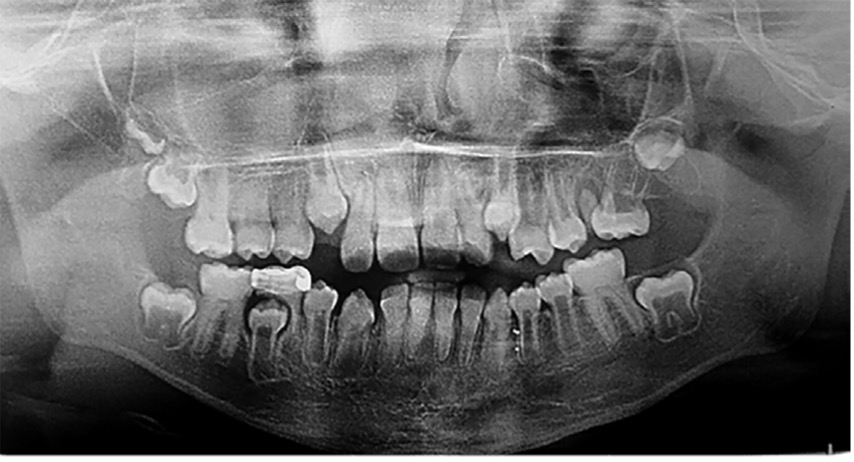

El examen clínico intraoral reveló alteración de la estructura y color de las piezas primarias, atrición y pérdida de la dimensión vertical (Figura 2). Radiográficamente se observó la presencia de coronas con marcada constricción cervical y raíces cortas (Figura 3). Presentaba alto riesgo cariogénico, por la presencia de lesiones de caries activas y dos restos radiculares, sumado a la anomalía estructural de la dentina (riesgo biológico específico) y bajo riesgo gingivoperiodontal. El riesgo socio-económico era alto por provenir de una familia con marcadas limitaciones económicas. Luego de la anamnesis, examen clínico y radiográfico, e interconsulta con el médico de cabecera se estableció el diagnóstico de DI Tipo I asociado a OI tipo I. Se planificó un tratamiento integral y preventivo con los objetivos de devolver forma y función, y proteger y evitar el desgaste de los tejidos conductas que pudieran interferir con el tratamiento.

Figura 2: Examen clínico intraoral del maxilar superior e inferior y vista anterior. Año 2007

Figura 3: Radiografía panorámica año 2007